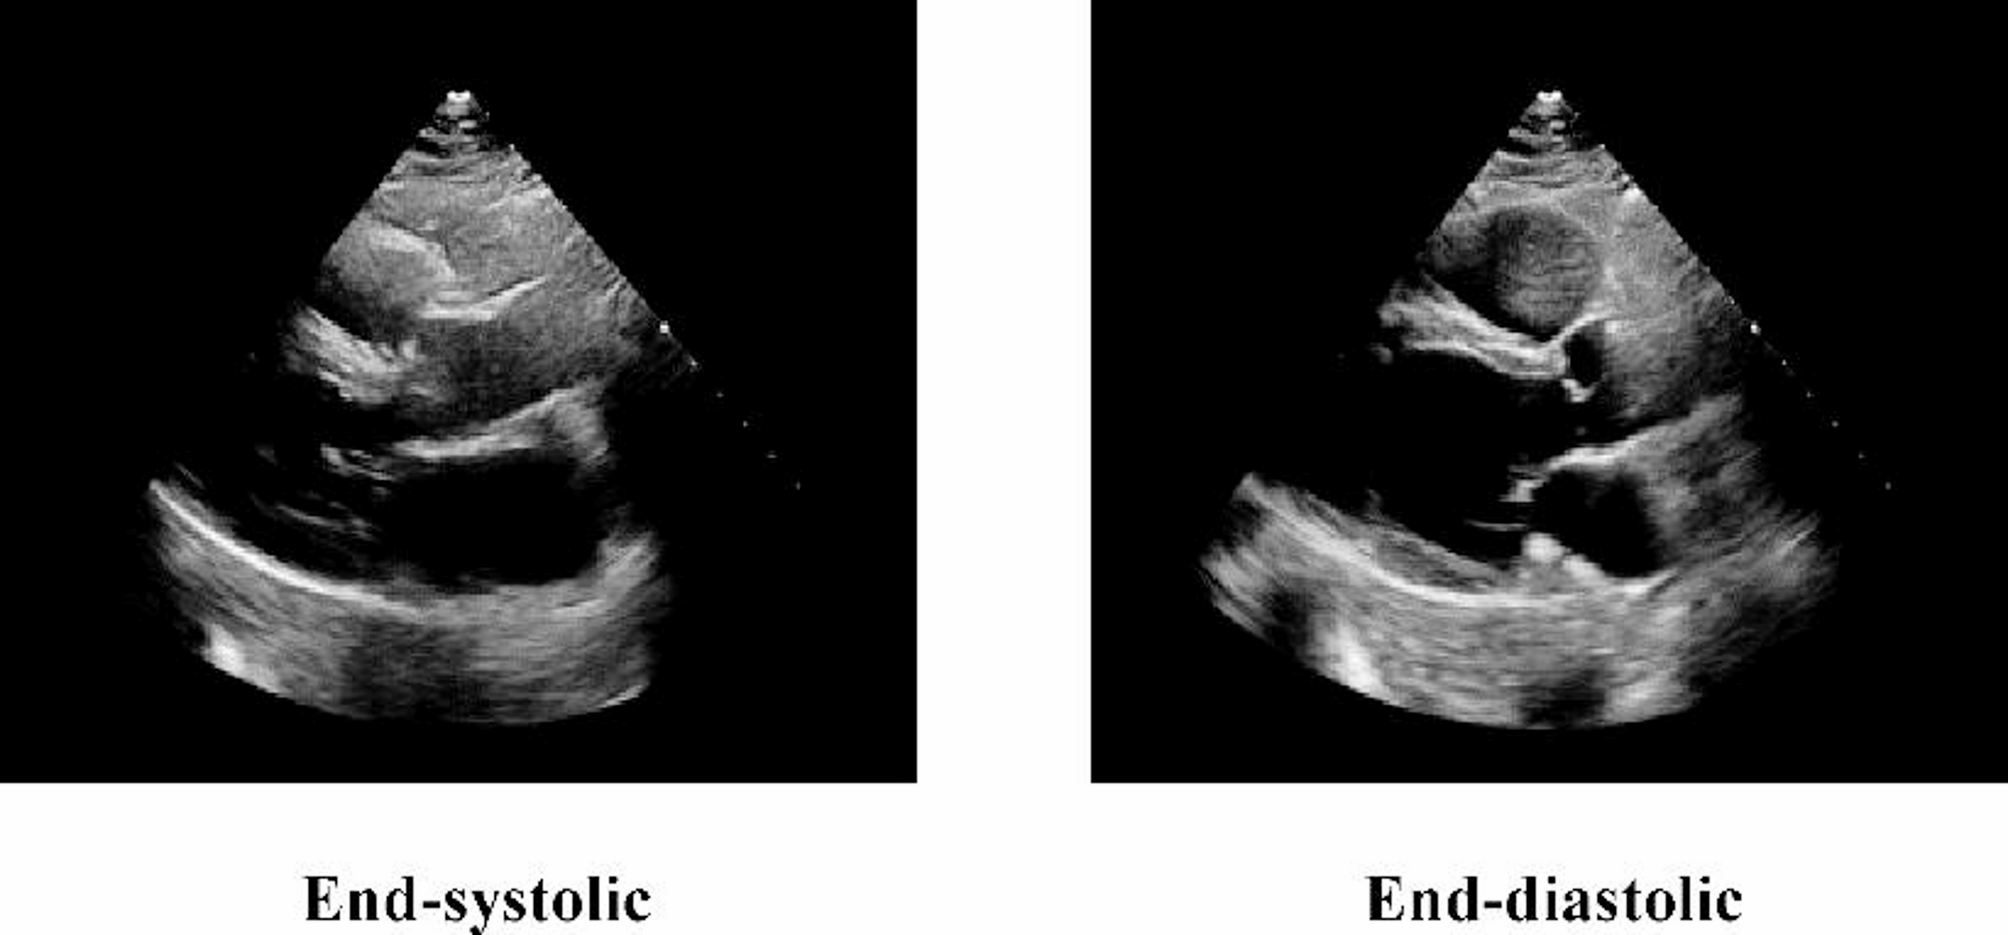

Fig. 1

Sample image from the EchoNet-LVH dataset (PLAX view). This image is shown at its original cropped resolution prior to model resizing.